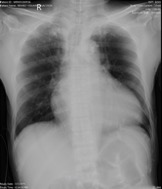

Relevant Test Results Prior to Catheterization

ECG was done which showed ST elevation at leads II,III,avF. Chest Xray showed cardiomegaly. Troponin I was elevated at 1310pg/ml. CBC showed leukocytosis (24.22 x 109/L) with neutrophilic predemoninance. 2D echo showed global hypokinesia with ejection fraction of 35%. Creatinine was elevated 208 umol/L with eGFR of 24mL/min.